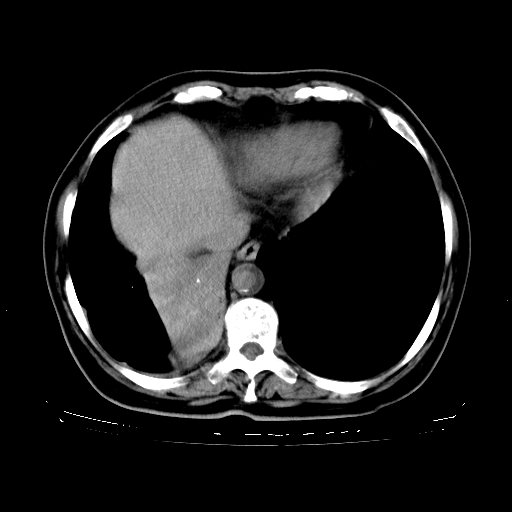

女,70岁,咳嗽、咳痰一个月,低热一周。

1、右肺占位,考虑周围型ca 。

2、右下肺软组织密度肿块影,考虑肺隔离征。

3、两肺肺结核(右肺下叶背段及左肺)。

4、主动脉夹层。

5、右侧少量胸腔积液。